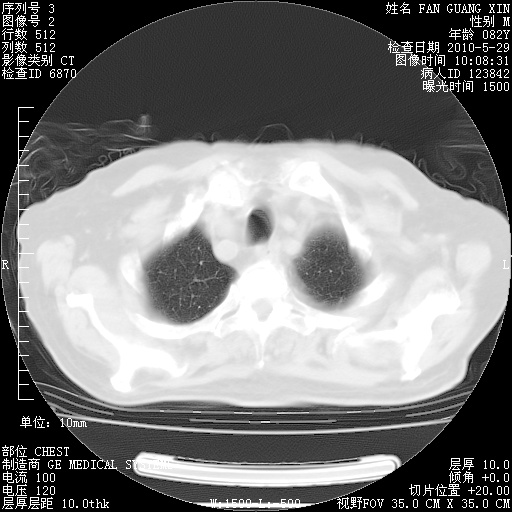

再治疗10天后的肺部CT

再治疗10天后的肺部CT 纵膈窗

肺部体征:呼吸25次/分,心率100次/分,呼吸音增粗。无干湿罗音。

血常规:15.36×10 [sup]9[/sup]/L  N0.92  L0.036  M0.045 ESR 27mm/h。

血生化:白蛋白33.30g/L  球蛋白23.67g/L  CRP 32.82mg/L 肝肾功能正常。电解质正常。

从白细胞总数和中性比例看好像合并感染。肺部纹理好像比上次多,支气管炎?其他感染?

阅读此次胸部CT,肺间质渗出性改变较入院时有吸收。目前从体温、白细胞、中性分叶明显增高,肯定存在细菌感染(发生医院感染哦,若无消化道及泌尿系统等感染的依据,肺部感染可能大)。若你院头孢哌酮舒巴坦钠耐药率较高,同意你的方案,若48小时体温仍高,可考虑使用碳青霉稀类抗菌药物,同时可予超声雾化、注意滴数时加大液体量。白蛋白33.30g/L较低哦,需加强营养等支持治疗。